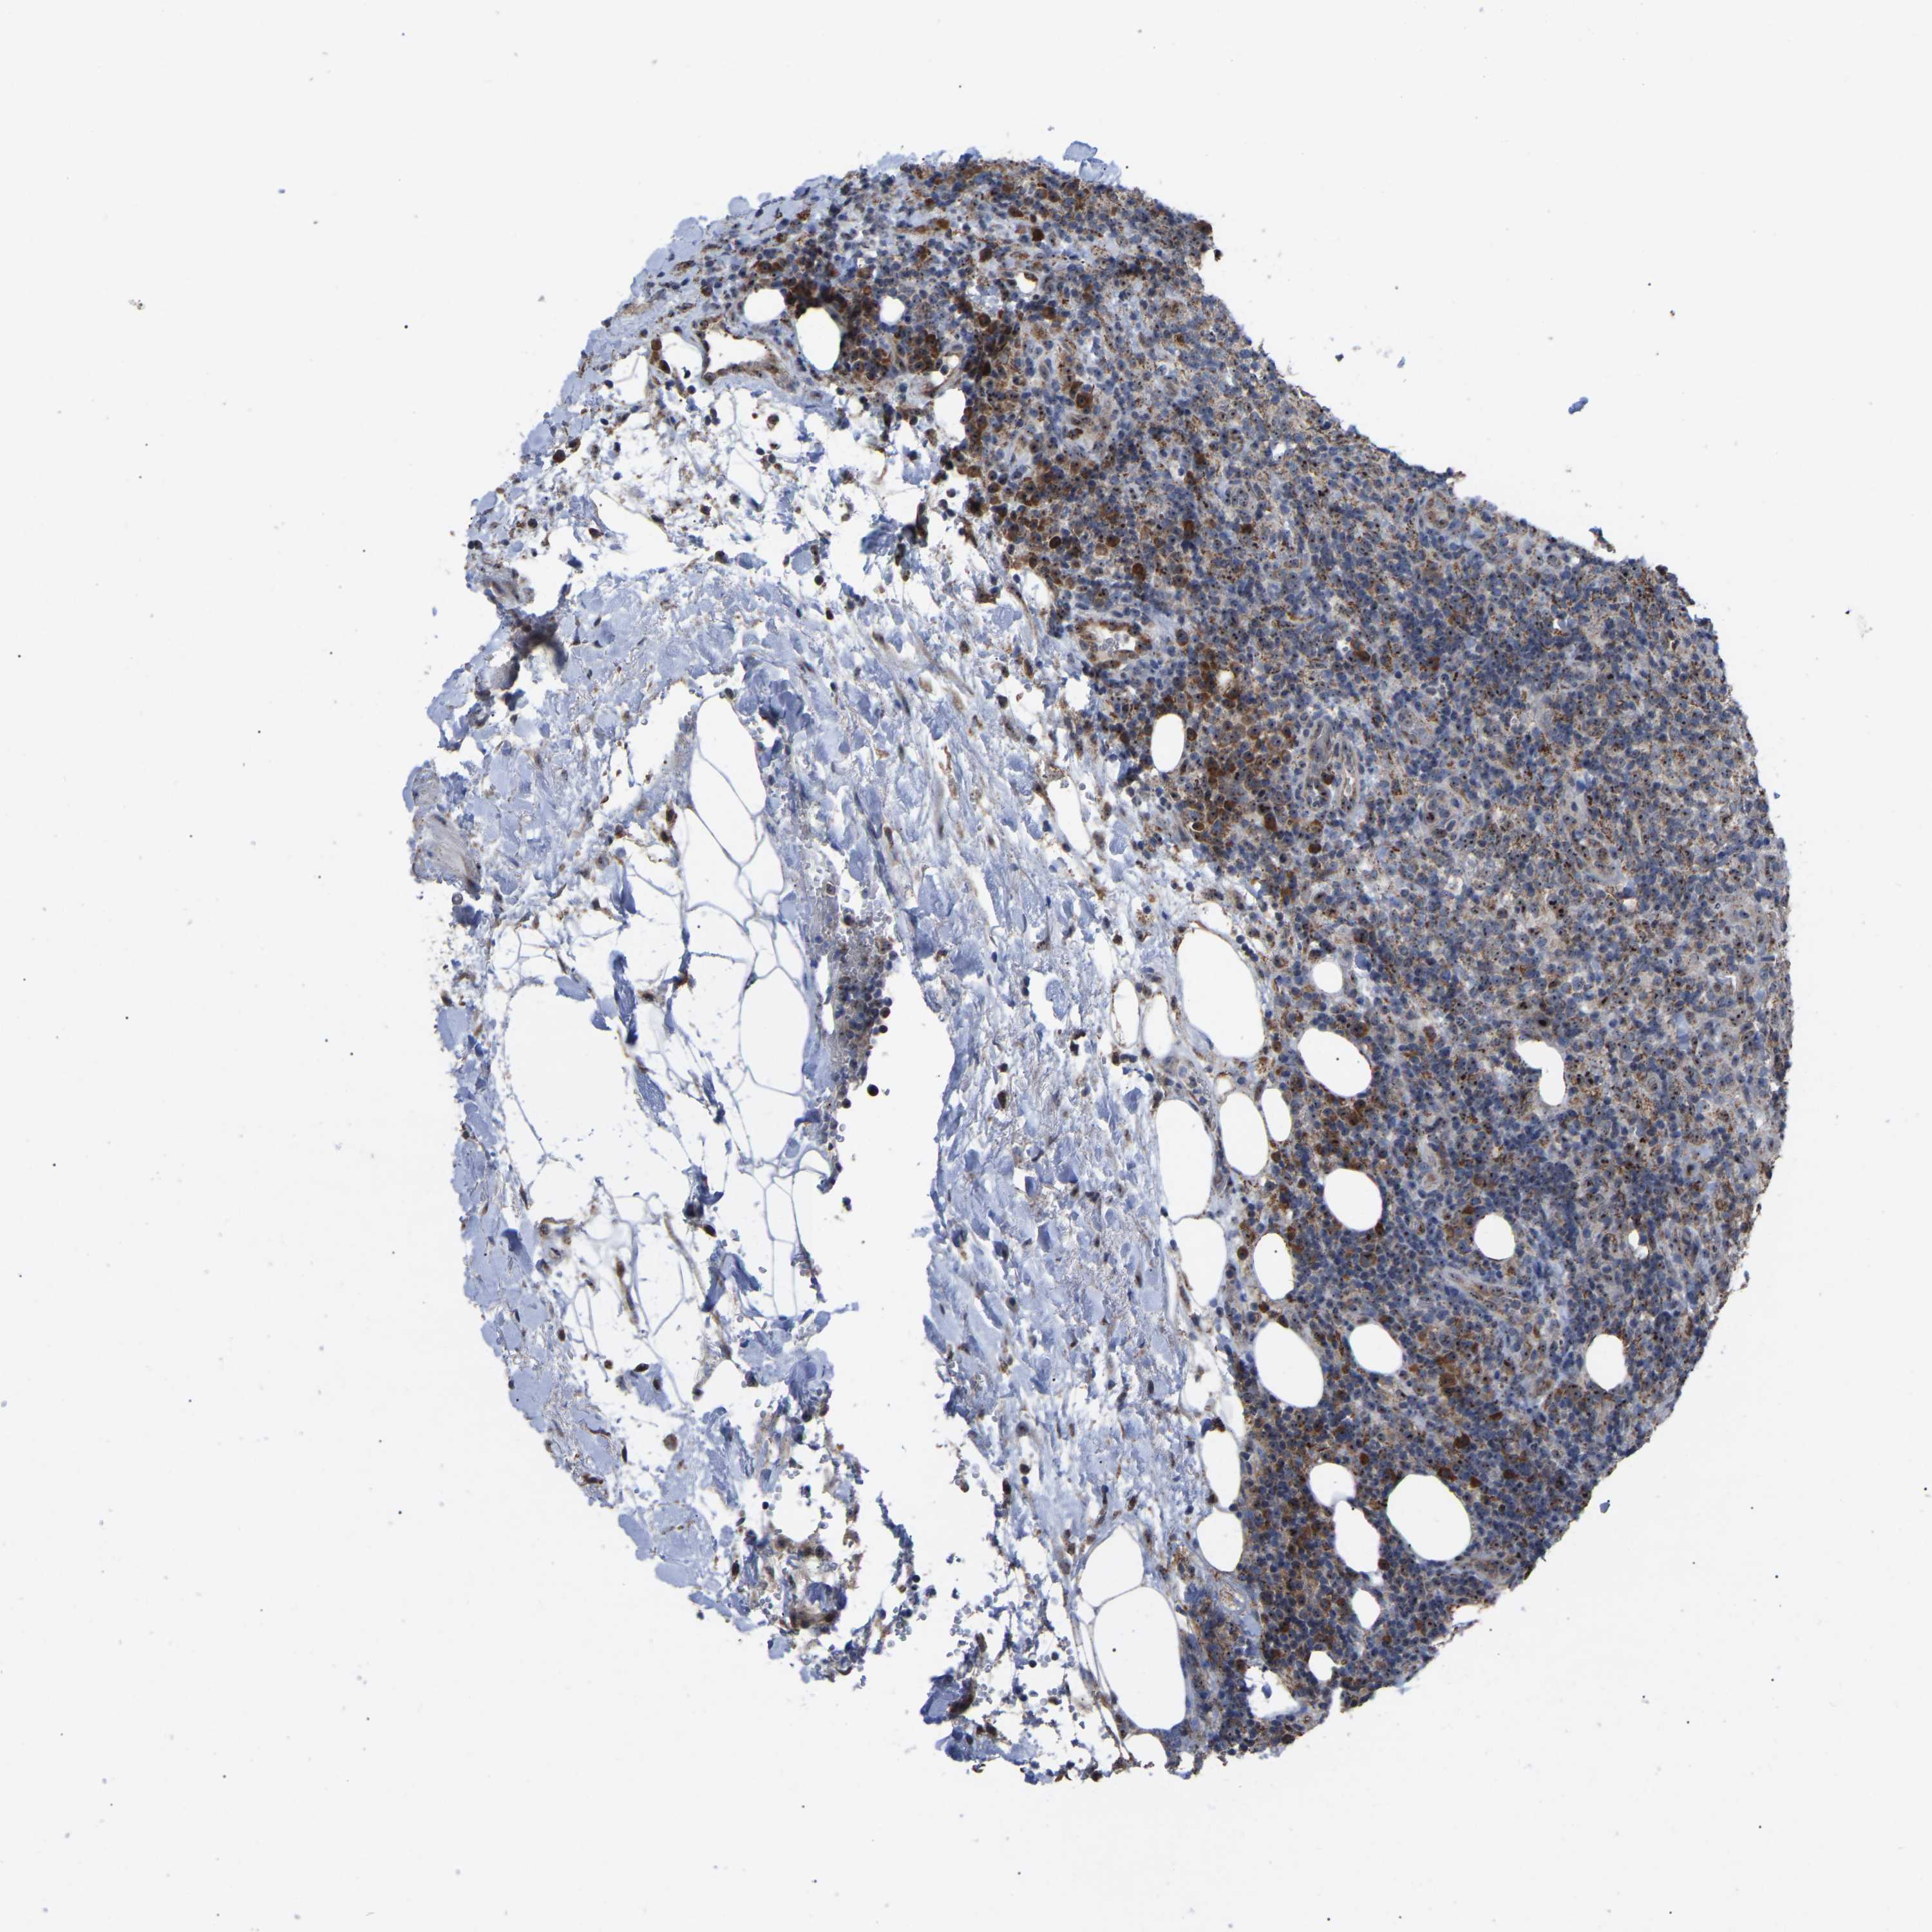

CANCER LYMPHOMA Show tissue menu

LYMPHOMA - Protein expressioni

A mouse-over function shows sample information and annotation data. Click on an image to view it in a full screen mode. Samples can be filtered based on level of antibody staining by selecting one or several of the following categories: high, medium, low and not detected. The assay and annotation is described here.

Each image is clickable and will lead to virtual microscopy that enables deeper exploration of all samples and also displays staining intensity scores, fraction scores and subcellular localization as well as patient and tissue information for each sample.

Antibody HPA018999

Hodgkin's disease, NOS

Malignant lymphoma, non-Hodgkin's type, High grade

Malignant lymphoma, non-Hodgkin's type, Low grade